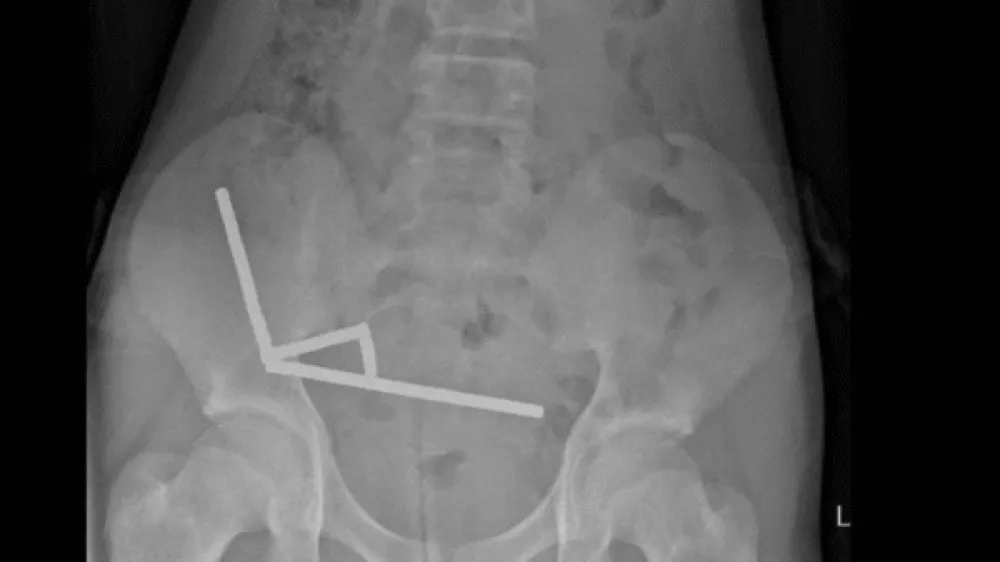

Diagnostični postopki so pokazali, da je pogoltnil precej več kot 100 magnetov. Ti so se po njegovem prebavnem sistemu združili v več verig, kar je prekinilo dotok krvi. Del črevesja so mu morali odstraniti, saj je tkivo odmrlo.

Z operacijo so odstranili verige magnetov v tankem in debelem črevesu. Deček je po operaciji dobro okreval in je po osmih dneh lahko odšel v domačo oskrbo.